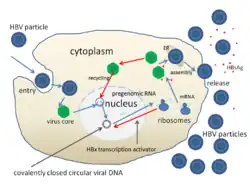

Hepatitis B, hepatitis C, and hepatitis D are transmitted when blood or mucous membranes are exposed to infected blood and body fluids, such as semen and vaginal secretions.[18] Viral particles have also been found in saliva and breastmilk. Kissing, sharing utensils, and breastfeeding do not lead to transmission unless these fluids are introduced into open sores or cuts.[30] Many families who do not have safe drinking water or live in unhygienic homes have contracted hepatitis because saliva and blood droplets are often carried through the water and blood-borne illnesses spread quickly in unsanitary settings.[31]

Hepatitis B and C can present either acutely or chronically.[18] Hepatitis D is a defective virus that requires hepatitis B to replicate and is only found with hepatitis B co-infection.[18] In adults, hepatitis B infection is most commonly self-limiting, with less than 5% progressing to chronic state, and 20 to 30% of those chronically infected developing cirrhosis or liver cancer.[32] Infection in infants and children frequently leads to chronic infection.[32]

Viral hepatitis

The pathway by which hepatic viruses cause viral hepatitis is best understood in the case of hepatitis B and C.[18] The viruses do not directly activate apoptosis (cell death).[18][60] Rather, infection of liver cells activates the innate and adaptive arms of the immune system leading to an inflammatory response which causes cellular damage and death, including viral-induced apoptosis via the induction of the death receptor-mediated signaling pathway.[18][60][61][62] Depending on the strength of the immune response, the types of immune cells involved and the ability of the virus to evade the body's defense, infection can either lead to clearance (acute disease) or persistence (chronic disease) of the virus.[18] The chronic presence of the virus within liver cells results in multiple waves of inflammation, injury and wound healing that over time lead to scarring or fibrosis and culminate in hepatocellular carcinoma.[60][63] People with impaired immune response are at greater risk of developing chronic infection.[18] Natural killer cells are the primary drivers of the initial innate response and create a cytokine environment that results in the recruitment of CD4 T-helper and CD8 cytotoxic T-cells.[64][65] Type I interferons are the cytokines that drive the antiviral response.[65] In chronic Hepatitis B and C, natural killer cell function is impaired.[64]

In the case of hepatitis B, blood tests exist for multiple virus antigens (which are different components of the virion particle) and antibodies.[77] The combination of antigen and antibody positivity can provide information about the stage of infection (acute or chronic), the degree of viral replication, and the infectivity of the virus.[77]